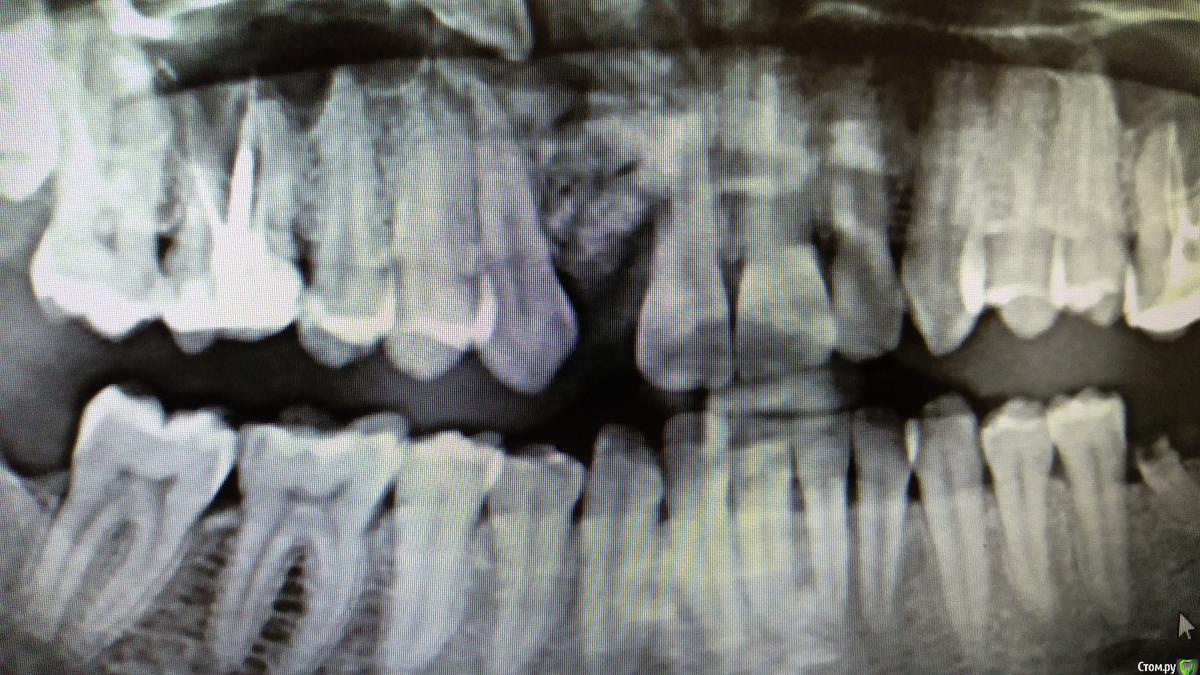

NickBulin Опубликовано 24 мая, 2018 Поделиться Опубликовано 24 мая, 2018 (изменено) Здравствуйте! Планировалась имплантация в области 1.2 зуба, кто нибудь сталкивался с подобной картиной?) В полости рта небольшое безболезненное уплотнение в проекции образования. Без кт, возможно ли предположить что это? Интересует дальнейшая тактика. Изменено 24 мая, 2018 пользователем NickBulin Ссылка на комментарий

NickBulin Опубликовано 25 мая, 2018 Автор Поделиться Опубликовано 25 мая, 2018 (изменено) На кт направил сразу. Ретенция 1.2. На его месте последние 10 лет носился съёмный протез "бабочка". Изменено 25 мая, 2018 пользователем NickBulin Ссылка на комментарий